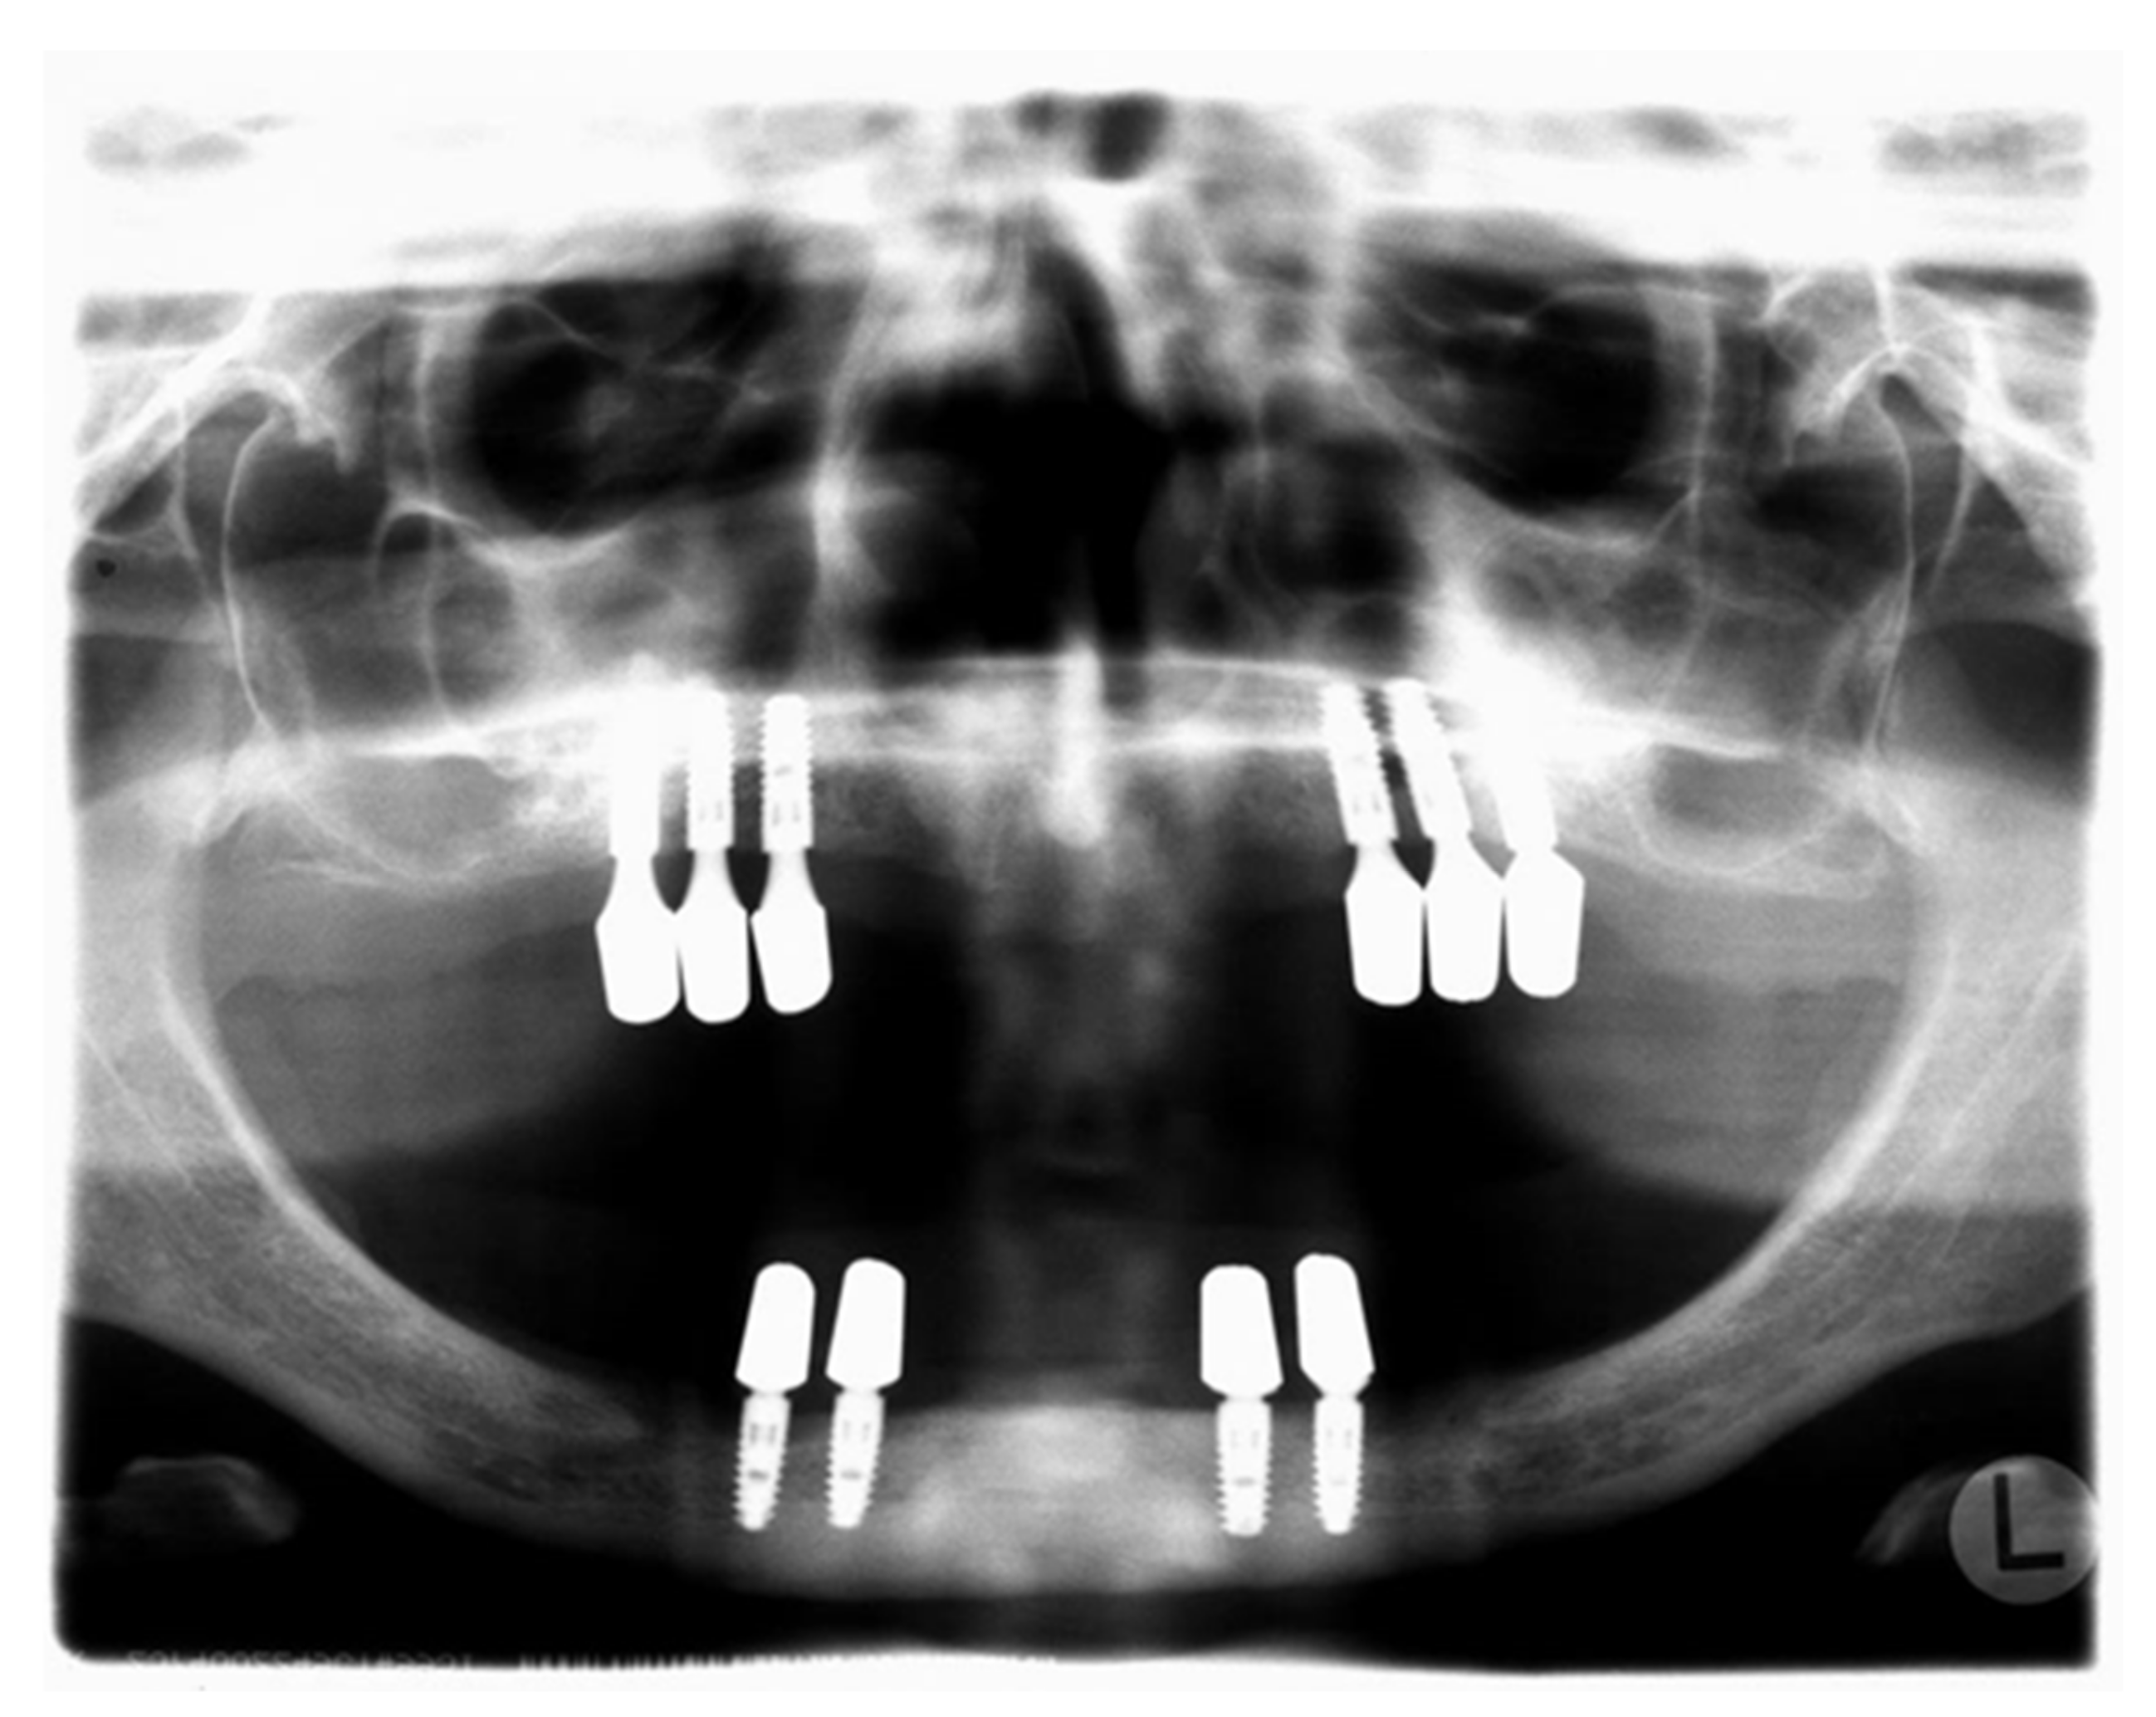

| Family | Patient | Implants In Situ (Number/Jaw/Type); Year Implants Were Placed; Follow-Up (Years) | Implants Lost (Number) | Bone Grafting (Yes/No/Material) | Prosthetic Restoration | Supportive Therapy (Yes/No/Main Contents) |

|---|---|---|---|---|---|---|

| A | 1 (♀/*1988) | 6× maxilla 4× mandible Ankylos® (Dentsply Friadent, York, PA, USA) (all Ø 3.5 mm, length 11 mm); Placed in 2007; 2.5 years | - | Yes (maxilla) Bio-Oss Block® (Geistlich, Wolhusen, Switzerland), autologous bone (zygomaticum), Bio-Gide® (Geistlich) | Removable telescopic crown-supported restoration (galvano) | no |

| A | 2 (♀/*1991) | 6× maxilla 4× mandible Ankylos® (Dentsply Friadent, York, PA, USA) (all Ø 3.5 mm, length 9.5 and 11 mm); Placed in 2010; 5 years | - | Yes (maxilla) Bio-Oss Block® (Geistlich), autologous bone (zygomaticum), Bio-Gide® (Geistlich) | Removable telescopic crown-supported restoration (galvano) | yes (but irregular): professional dental cleaning once a year; measuring of PPD (irregular), subgingival cleaning (glycine) in case of increased PPD+BOP |

| B | 3 (♀/*1974) | 4× maxilla 8× mandible maxilla: Astra® (Dentsply, York, PA, USA) mandible: Brånemark® (Nobel Biocare, Kloten, Switzerland) Placed in 1992; re-implantation maxilla in 2008 and 2010; 20 years (mandible), 4/2 years (maxilla) | 4 | Yes (maxilla) Autologous bone (iliac crest) | Removable bar-carried restoration | yes: professional dental cleaning every 3 months; no measuring of PPD, no subgingival cleaning; systemic amoxicillin + clavulanic acid and metronidazole for seven days twice a year; no professional supportive therapy |

| B | 4 (♀/*1983) | 1× maxilla 4× mandible 1 disc-shaped implant (unknown manufacturer); all others: Brånemark® (Nobel Biocare, Kloten, Switzerland) implants Placed in 1993; 19 years | 11 | Yes (maxilla) Autologous bone and bone substitute (unknown material) | Removable telescopic crown- and ball-shaped head-supported restoration | yes: professional dental cleaning every 3 months; no measurement of PPD, no subgingival cleaning; systemic amoxicillin + clavulanic acid and metronidazole for seven days twice a year; no professional supportive therapy |

| C | 5 (♂/*1971) | 5× maxilla 6× mandible 1 Biomet® 3i implant, all other: IMZ® implants (Dentsply, York, PA, USA); Placed in 1992; 20 years | Several implants were lost, number unknown | Yes (maxilla) (unknown material) | Removable bar-supported (maxilla) and removable telescopic crown-supported restoration (mandible) | no |

| Patient | Bone Loss 0− < 25% | Bone Loss 25− < 50% | Bone Loss ≥ 50% |

|---|---|---|---|

| 1 | 75% | 25% | 0% |

| 2 | 95% | 5% | 0% |

| 3 | 29% | 46% | 25% |

| 4 | 60% | 20% | 20% |

| 5 | 13% | 55% | 32% |